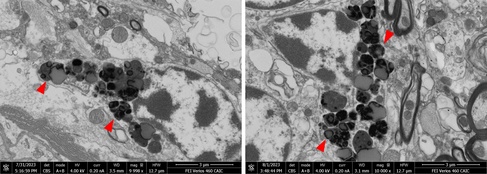

Lactating mammary gland - methylene blue staining of a semi-thick section (left) and corresponding EM image of an adjacent thinsection in SEM blockface imaging (right) – tissue derived from FFPE material (FFPE block kindly donated by the team of the Cambridge PDN Histology Teaching Room, EM by CAIC).

If intended initially for histology only, tissues are usually not fixed optimally for EM studies, and the material available is either preserved in formalin or as a FFPE block (formalin-fixed, paraffin-embedded). Formalin-fixed material can give very good results in EM, especially if the time lag between tissue excision and fixation was kept very short. In contrast, expectations as to EM image quality have to be moderated when working from FFPE blocks. These tissues have already seen extensive processing, including solvent dehydration and infiltration with paraffin and have to undergo similar procedures a second time to become an EM resin block. The solvent dehydrations in particular can extract tissue lipids and membrane structures, resulting generally in much poorer tissue morphology compared to tissues processed optimally for EM from the start.

SEM blockface image of an alveoli of a lactating mammary gland (left) and detail of a likely secretory cell in the surrounding tissue away from the alveolus (right). Due to working from FFPE material, most cytoplasmic membranes have been removed, but due to the decoration with protein-rich ribosomes, the structure of the rER is still recognizable. Other well-preserved structures are usually the nuclei and collagen bundles/fibrils of the extracellular matrix (red arrowheads).